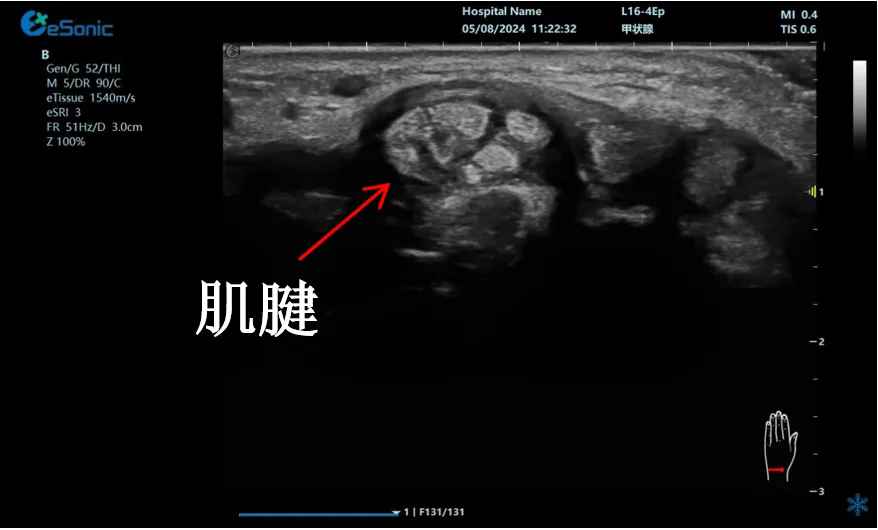

mFlow?技术在腱鞘炎诊疗中的应用

【背景】:左手腕关节第四腔室腱鞘炎。

【痛点】:普通彩色多普勒不敏感,只能看到细小点状血流,容易被忽略,难以进行分级诊断和疗效评估。

【方案】:新航娱乐医疗(ESI)超微血流技术可以看到腔室内肌腱周围环状血流,可充分提示:

1、处于炎症活动期;

2、根据血流进行分级诊断提示1级;

3、治疗后根据血流多少评估疗效(见右下图:治疗10天后复查超声,微血流图像血供消失)。